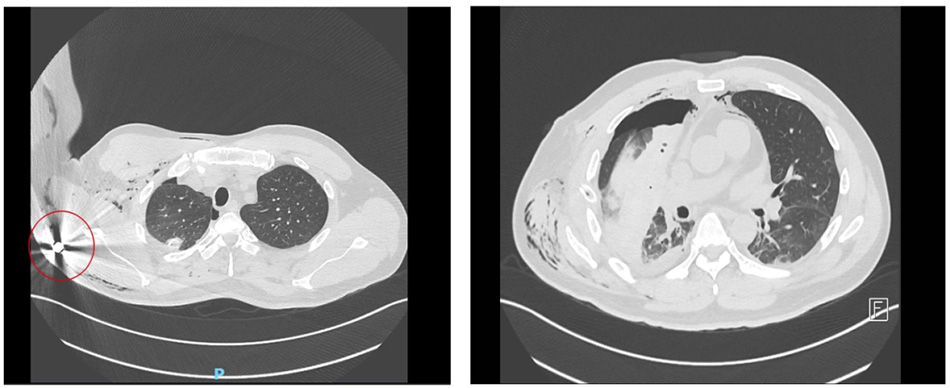

A chest CT scan revealed a surprising finding: the bullet was still lodged inside his body after having passed through the thoracic cavity.

The bullet pierced and destroyed the patient’s right lung lobe before becoming lodged inside the body

“This was a solid bullet, unlike bomb or mine fragments that shatter on impact. As it travels, the bullet spins, creating a wound that’s narrow at the entry but much wider at the exit, destroying multiple structures along its path. That’s also why the bleeding wouldn’t stop. The bullet entered through the front of the chest, passed through the thoracic cavity, pierced both lung lobes, and lodged near the scapula. It tore the pericardium but fortunately missed the heart and major blood vessels,” explained Dr Trung.